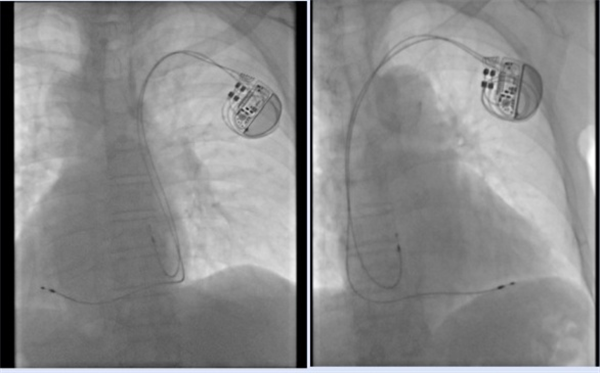

汪大爷最终被诊断为高度房室传导阻滞、镜面右位心和慢性心衰,病情十分危险。心血管内科团队评估后认为,若不及时植入心脏起搏器,汪大爷随时面临心衰加重和猝死的风险。尽管心脏起搏器植入术在池州市第二人民医院是常规手术,但为“镜面人”实施手术难度却极高。医生需要将手术习惯和技巧进行180度“转位”,这不仅要求医生有过硬的基本功和扎实的理论基础,还需对解剖结构和影像学检查熟练掌握,否则稍有不慎就会造成严重的脏器损伤。